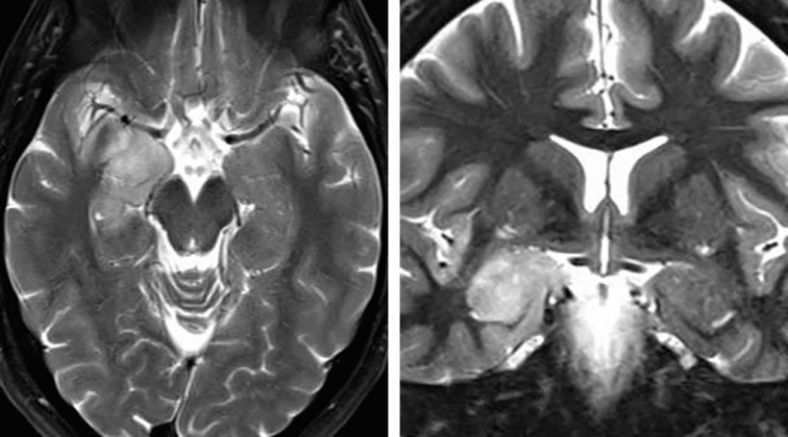

图1. 笔者更偏向于应用SA处理位于杏仁核、钩突及海马前部的肿瘤,尤其是优势半球侧;但针对颞叶内侧硬化症,并不认为SA较标准颞叶前内侧、杏仁核-海马切除术有更显著效果。